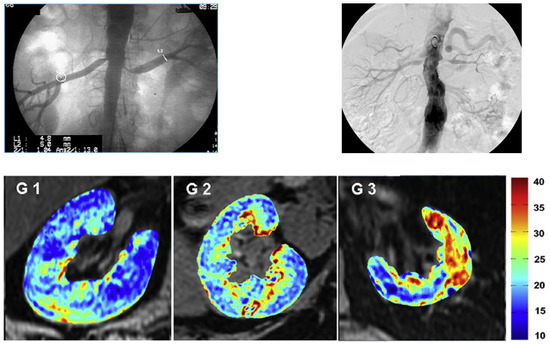

- Saad, A.; Crane, J.; Glockner, J.F.; Herrmann, S.M.S.; Friedman, H.; Ebrahimi, B.; Lerman, L.O.; Textor, S.C. Human renovascular disease: Estimating fractional tissue hypoxia to analyze blood oxygen level-dependent MR. Radiology 2013, 268, 770–778. [Google Scholar] [CrossRef]

- Textor, S.C.; Glockner, J.F.; Lerman, L.O.; Misra, S.; McKusick, M.A.; Riederer, S.J.; Grande, J.P.; Gomez, S.I.; Romero, J.C. The use of magnetic resonance to evaluate tissue oxygenation in renal artery stenosis. J. Am. Soc. Nephrol. 2008, 19, 780–788. [Google Scholar] [CrossRef]

- Gloviczki, M.L.; Glockner, J.F.; Lerman, L.O.; McKusick, M.A.; Misra, S.; Grande, J.P.; Textor, S.C. Preserved oxygenation despite reduced blood flow in poststenotic kidneys in human atherosclerotic renal artery stenosis. Hypertension 2010, 55, 961–966. [Google Scholar] [CrossRef]

- Gloviczki, M.L.; Glockner, J.F.; Crane, J.A.; McKusick, M.A.; Misra, S.; Grande, J.P.; Lerman, L.O.; Textor, S.C. Blood oxygen level-dependent magnetic resonance imaging identifies cortical hypoxia in severe renovascular disease. Hypertension 2011, 58, 1066–1072. [Google Scholar] [CrossRef] [PubMed]